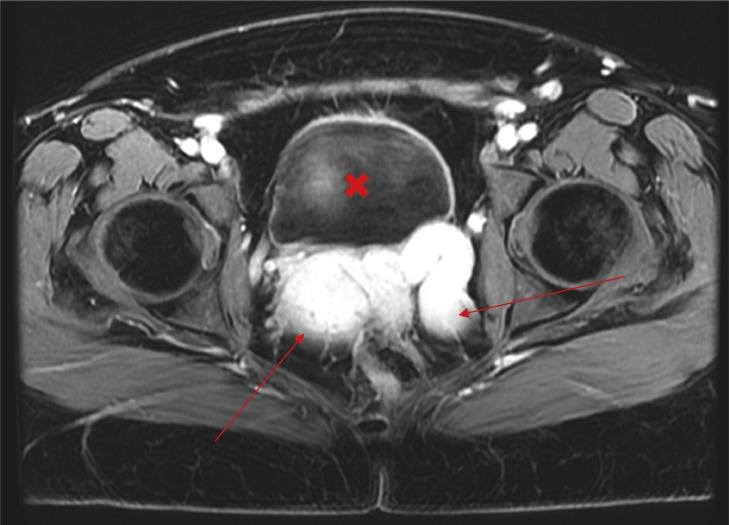

The inferior vena cava (IVC) is the main conduit of venous return to the right atrium from the lower extremities and abdominal organs. Agenesis of the IVC has an incidence of <1% in the general population [1], although it has been reported in the literature as occurring in up to 8.7% of the population [2]. Patients with absent IVC may present with symptoms of lower extremity venous insufficiency [6], idiopathic deep venous thrombosis [7], or pelvic congestion syndrome. To our knowledge there have only been a few cases reported in the literature of agenesis of the IVC associated with pelvic congestion syndrome [3,10,11]. We present another interesting case of pelvic congestion syndrome due to absent IVC.

下腔静脉(IVC)是下肢和腹部器官静脉血回流至右心房的主要通道。下腔静脉缺如在普通人群中的发生率<1%[1],尽管文献报道其发生率高达8.7%[2]。下腔静脉缺如的患者可能出现下肢静脉功能不全[6]、特发性深静脉血栓形成[7]或盆腔淤血综合征的症状。据我们所知,文献中仅报道了少数几例下腔静脉缺如合并盆腔淤血综合征的病例[3,10,11]。我们在此呈现另一例因下腔静脉缺如导致盆腔淤血综合征的有趣病例。